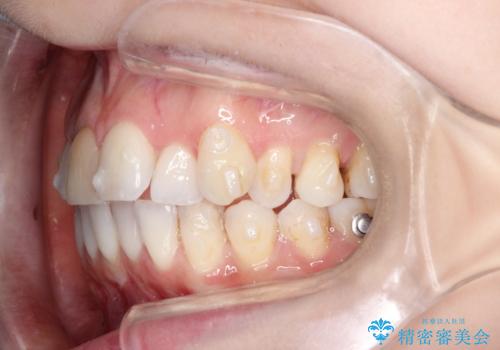

インビザラインによる非抜歯での八重歯の矯正

- 左上の八重歯と、上の歯のがたつきを主訴に来院されました。

上の奥歯を後方に移動させてスペースを作るのと、歯と歯の間をわずかに削り歯を並べる計画としました。

非常に強力的な患者様であったので、上下の正中も合わせ、ガタガタも改善することができました。